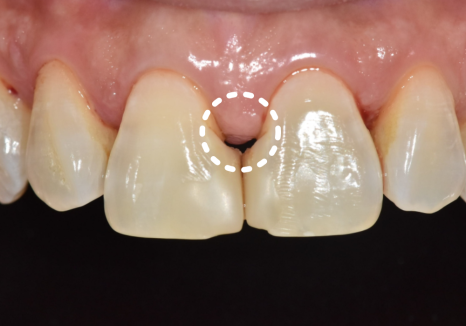

실제로 1년 전 초진 사진과

최근 사진을 비교해 보니,

잇몸 퇴축이 눈에 띄게 진행되면서

블랙 트라이앵글의 크기가

이전보다 확연히 커진 상태였습니다.

240716 / 250318

이로 인해

음식물이 반복적으로 끼고,

양치가 점점 어려워지면서

식사 후 불쾌감이 계속될 수밖에 없었던 것이죠.